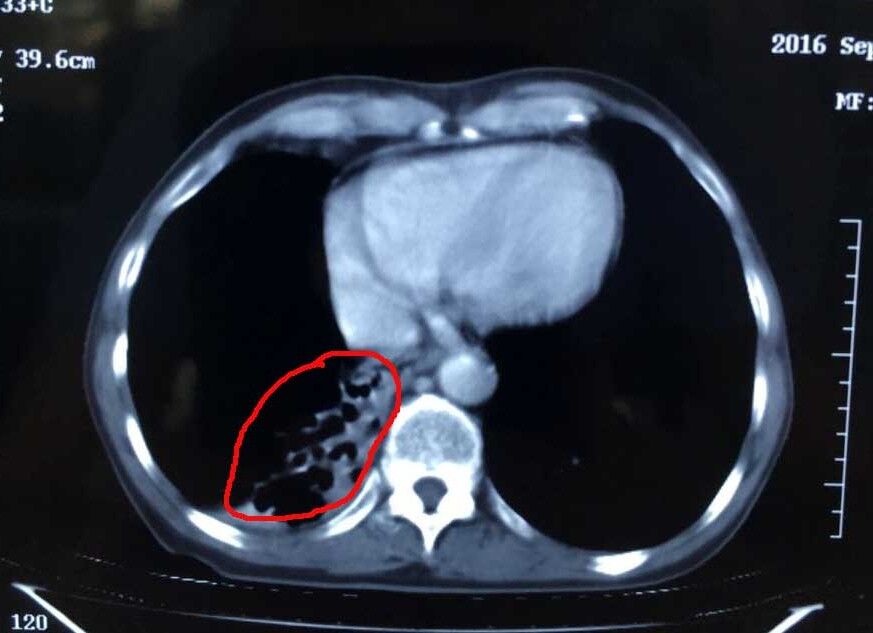

肿瘤治疗后